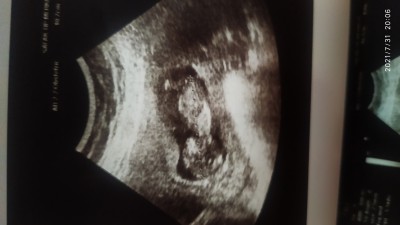

Kızlar burda 12+4 günlük gebeyim doktor bişey demedi sizce erkekmi kızmı

Gebelik haftası 12+4

Erkege benziyor